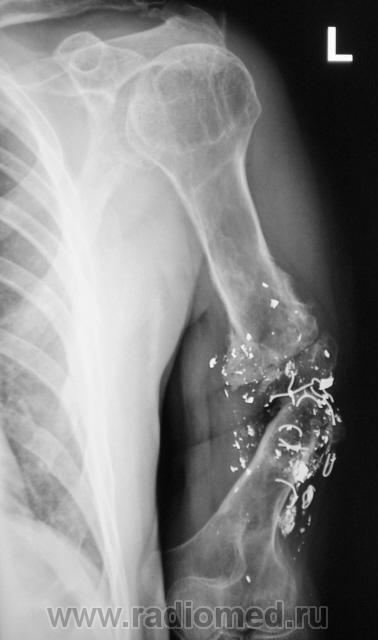

прямо помойка какая-то, но из всего этого можно определить элементы серкляжных швов, если сохранилась целостность лучевого нерва, то фунция у этого больного вероятно сносная, получилось подобие коленного сустава верхней конечности( даже надколенник есть) судя по плечевому суставу больной активно пользуется конечностью

Нда...Боюсь даже предположить - состояние после металлоостеосинеза?!

Ужас... Меня впечатлить трудно, но тут проняло... Есть малый шанс, что это - и последствие огнестрела, дробовик с металлической дрянью, но врядли...

Это видимо результат минно- взрывной травмы.